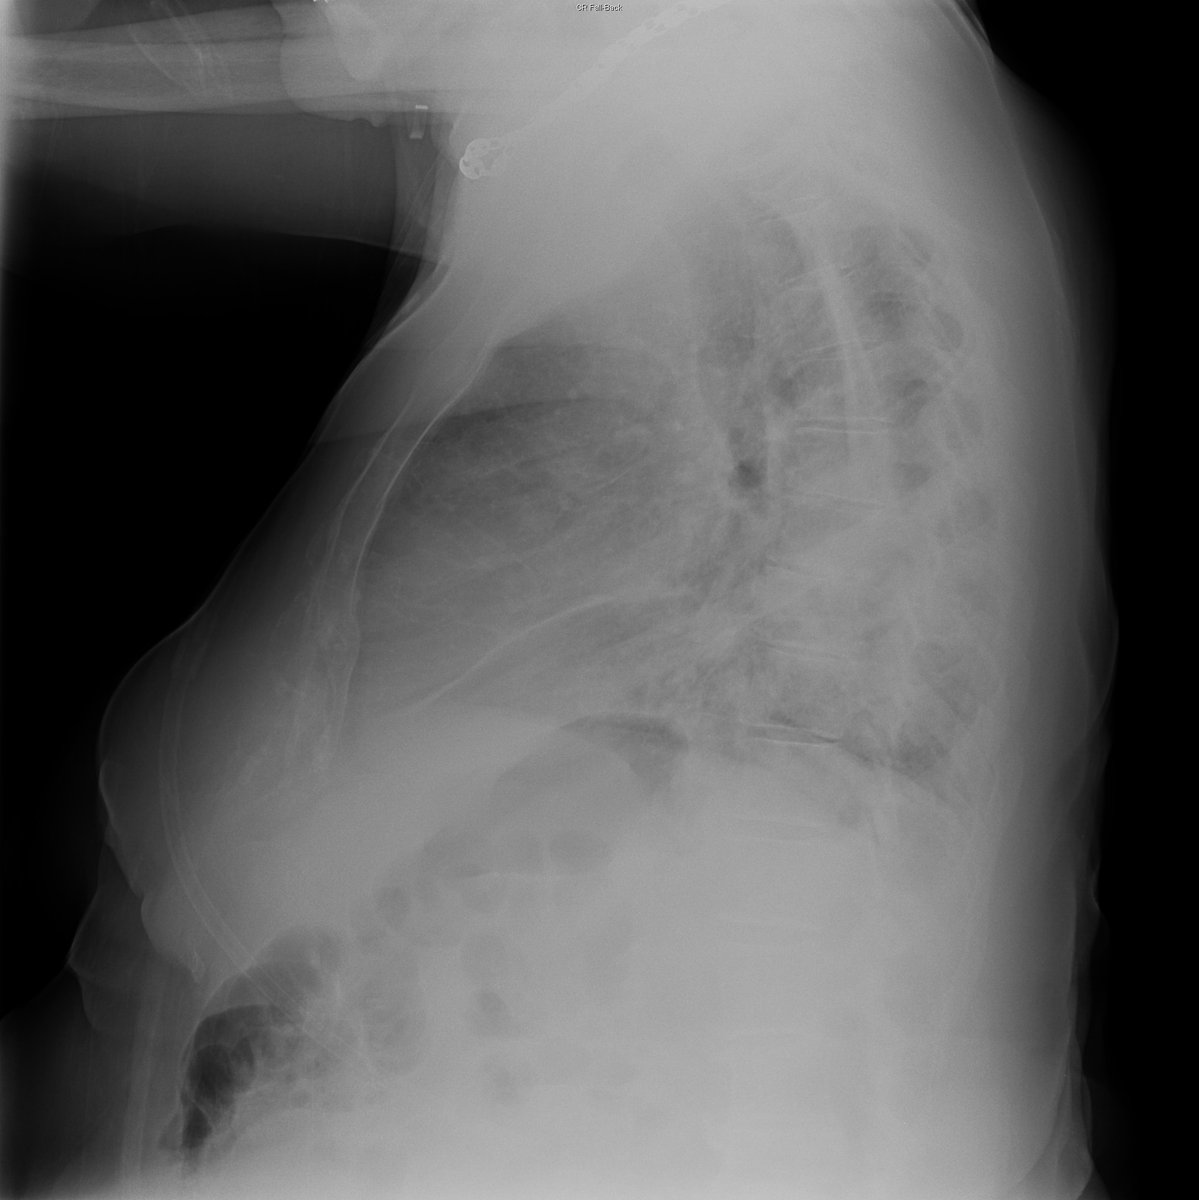

Case 1. 68yo female. Cough and fever.